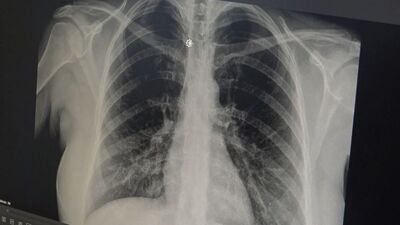

Göğüs Hastalıkları Uzmanı Prof. Dr. Tevfik Özlü, akut bronşitin yaygınlaştığına dikkati çekerek tavsiyelerde bulundu. Prof. Dr. Özlü, akut bronşitte ilk belirtilerinin boğaz ağrısı, hafif ateş ve burun akıntısı olduğunu ancak enfeksiyonun bronşlara inmesi ile göğüs ağrısı ve şiddetli öksürüğün ortaya çıktığını belirtti. Özlü, akut bronşitin hafif seyirli ve tedavi edilebilir bir hastalık olduğunu ifade edip, hastaları da hekimlere başvurması konusunda uyardı.

Prof. Dr. Özlü, akut bronşitin solunum yolu virüslerinden kaynaklı bir hastalık olduğunu ifade ederek, "Şu sıralar çok sık gördüğümüz bir hastalık. Genelde hastalar şöyle tarif ediyorlar; 'Öncelikle boğazımda bir ağrı oldu, hafif ateşim, burun akıntım, hapşırmam, geniz akıntım oldu ve öksürüğüm var. 2-3 gündür de göğsüme indi. Nefes alıp verirken bir sızlama oluyor. Bir ağrı hissediyorum. Adeta göğsümde çalı var gibi, nefes alıp verirken oraya takılıyor gibi hissediyorum' diyorlar. Enfeksiyonun göğse indiğini ifade ediyorlar. Aslında doğru olan da budur. Çünkü akut bronşit; genellikle solunum yolu virüslerinden kaynaklanan bir enfeksiyon hastalığıdır. Bu enfeksiyon sadece üst solunum yollarıyla; burunda boğazda sınırlı kalmıyor. Alt solunum yollarımıza, bronşlarımıza iniyorsa, bu tür semptomlarla kendini gösteriyor" dedi.

Akut bronşitte en belirgin semptomun öksürük olduğunu vurgulayan Prof. Dr. Tevfik Özlü, "Kuru öksürük ya da balgamlı öksürük şeklinde olabilir. Bazen hırıltı ve nefes darlığı yaşanabilir. En çok rahatsız eden semptomsa inatçı öksürüklerdir. Genelde yüksek ateş durum bozukluğu yapmaz, hafif bir tablodur. Ama bazen bakteriyel enfeksiyonlar da üzerine eklenebilir. Yüksek ateş, halsizlik, kırgınlık ortaya çıkabilir" diye konuştu.

Bronşitin genelde hafif seyirli bir hastalık olduğunu ancak belirtilerin artması halinde hekime başvurulması gerektiğini ifade eden Özlü, "Eğer altta bir kronik hastalık; astım ya da KOAH (Kronik Obstrüktif Akciğer Hastalığı) gibi bir akciğer hastalığı varsa, kronik hastalığın akut alevlenmesi buna eşlik edebilir ve genel durumu bozabilir. Akut bronşit hastada; nefes darlığı, hırıltılı solunum, halsizlik, bitkinlik, yüksek ateş gibi ağır semptomlarla kendini gösterebilir. Böyle ağır bir durum varsa ya da zeminde kronik bir hastalık var ve ona bağlı semptomlarda alevlenme söz konusu ise o zaman mutlaka bir hekime başvurmak gerekir. Genel itibarıyla hafif seyirli, tedavi edilebilir bir hastalık olduğunu söylemek isterim" dedi.